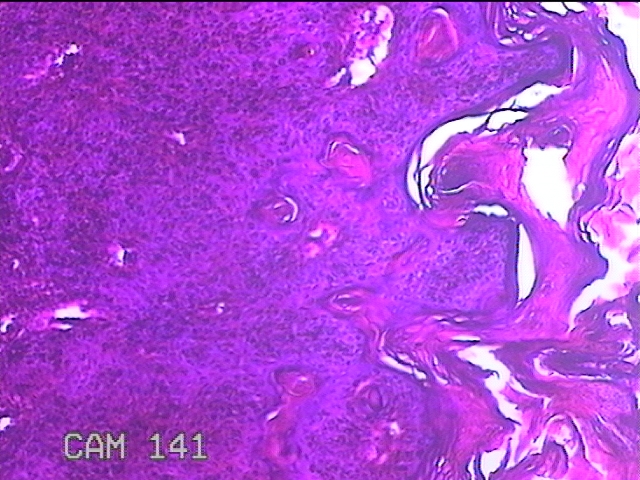

性别

女

年龄

39岁

临床诊断

皮下结节

一般病史

发现左臀部多发性结节5年余。

标本名称

左臀部结节

大体所见

灰白粉红色结节0.7x0.3x0.2cm一个,表面糜烂。

图2